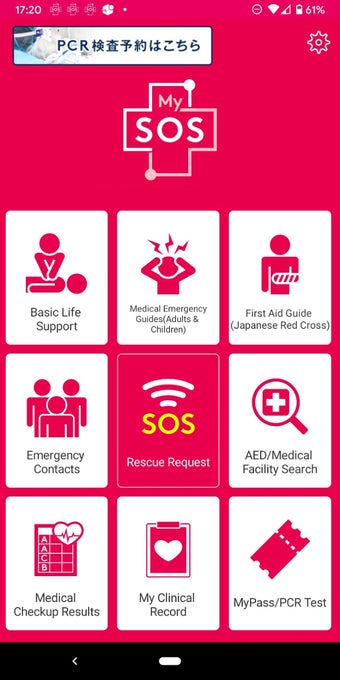

MySOS เป็นแอปพลิเคชันบนมือถือที่ช่วยให้ผู้ใช้เข้าถึงข้อมูลและบริการที่เกี่ยวข้องกับสุขภาพและการดูแลรักษาสุขภาพในประเทศญี่ปุ่น มันถูกออกแบบมาเพื่อให้การช่วยเหลือในกรณีฉุกเฉินทางการแพทย์และรองรับการดูแลสุขภาพและการบริการฉุกเฉิน

เมื่อคุณใช้ MySOS คุณสามารถเข้าถึงข้อมูลและบริการที่เกี่ยวข้องกับสุขภาพและการดูแลรักษาสุขภาพในประเทศญี่ปุ่นได้ คุณสามารถส่งคำขอความช่วยเหลือไปยังผู้ที่คุณไว้วางใจ เช่นครอบครัวหรือเพื่อนของคุณ คุณยังสามารถยืนยันตำแหน่งของ AED หรือโรงพยาบาลที่คุณต้องการไปเยี่ยมชมและส่งคำขอความช่วยเหลือไปยังผู้ที่คุณไว้วางใจได้